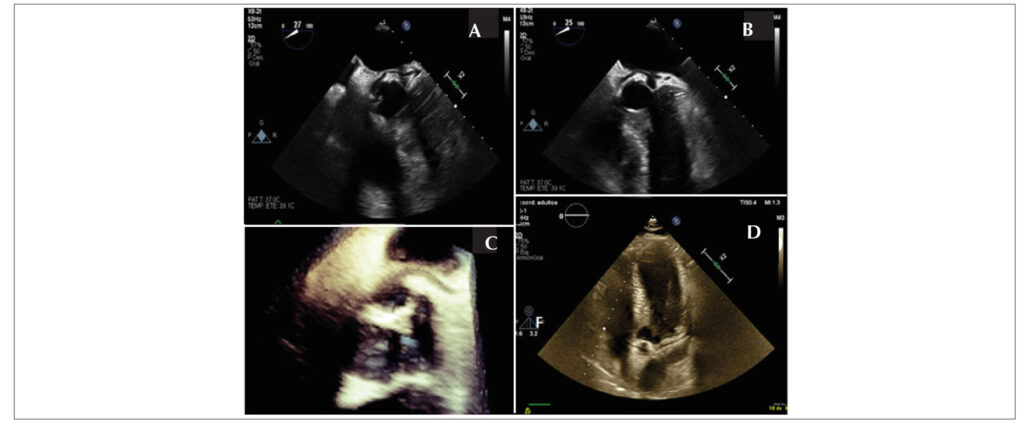

Retroaortic Circunflex Coronary Artery Appearance on Transesophageal Echocardiography

The retroaortic anomalous coronary (RAC) sign is an unknown finding that has been described on transthoracic echocardiography as an echogenic tubular structure located on the atrial side of the atrioventricular sulcus. Here we present a case in which the RAC sign on transesophageal echocardiography (TEE). Knowledge of RAC sign and its evaluation on TEE increases sensitivity and specificity and provides the opportunity to assess high-risk anatomic features that are important in evaluating the risk of sudden death.